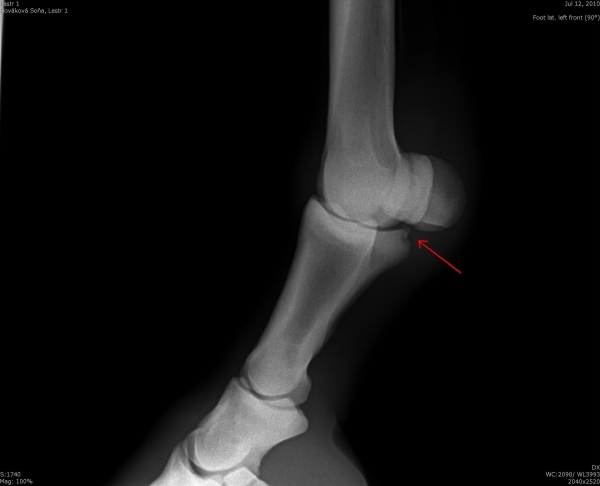

Čip ve spěnkovém kloubu na pánevní končetině

Fragment na spěnkové kosti